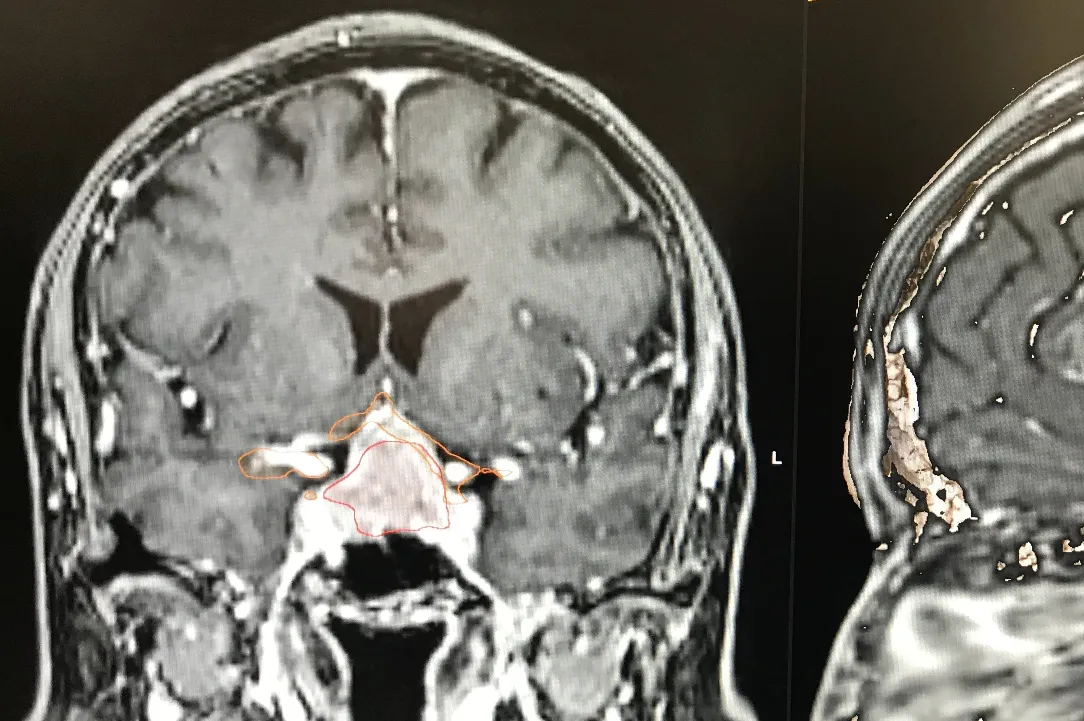

Les adénomes hypophysaires sont majoritairement des tumeurs bégnines qui se développent à partir de la glande hypophysaire.

On peut les catégoriser par leur activité et par leur volume. En effet, ceux-ci peuvent secréter de manière excessive des hormones hypophysaires ou peuvent, par leur volume, comprimer les structures fonctionnelles et, en particulier, le nerf optique et le chiasma.

Les adénomes secrétants sont habituellement découverts de manière plus précoce et sont le plus souvent catégorisés comme des micro-adénomes. Leur traitement est, dans un premier temps, le plus souvent médicamenteux et, en cas d’échappement du traitement médical, peut être chirurgical. Il nécessite dès lors une étroite collaboration entre les endocrinologues et les neurochirurgiens.

Les adénomes non-secrétants sont souvent découverts soit de manière fortuite lors d’une imagerie cérébrale, soit en lien avec leur volume excessif. On parle alors de macroadénomes qui sont responsables de troubles le plus souvent visuels par compression du nerf optique et ou du chiasma. Leur traitement est chirurgical s’ils sont symptomatiques. L’acte chirurgical consiste à l’exérèse de la tumeur via les cavités nasales et le sinus sphénoïdale (voie transnasale, transphénoïdale). L’abord peut se faire sous endoscope ou microscope. La tendance actuelle est d’utiliser la voie endoscopique en étroite collaboration avec l’équipe d’ORL. Dans certaines situations, un traitement combinant l’exérèse chirurgicale et un traitement par radiochirurgie peut être discuté en concertation oncologique multidisciplinaire. Vous retrouverez au sein de notre service de Neurochirurgie du CHIREC, l’ensemble de ces collaborations possibles.